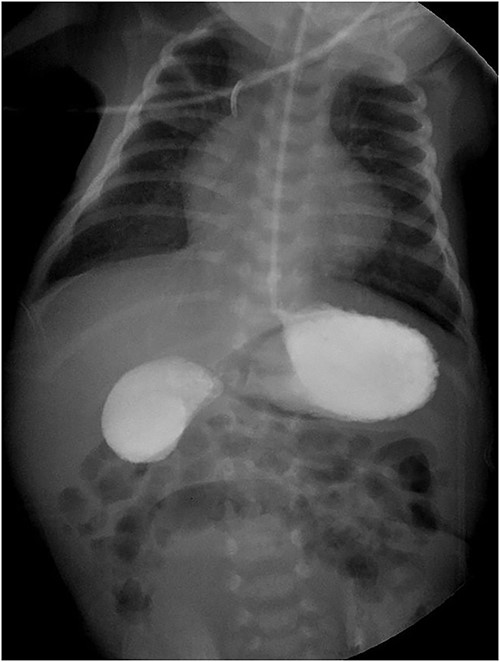

The gastroduodenal series showed data compatible with a duodenal membrane between the second and third portions of the duodenum (Fig. 1). Based on the above, exploratory laparotomy was scheduled, where in the transoperative period, the pancreas was found completely wrapping the second portion of the duodenum (Fig. 2A), so it was decided to perform a diamond-shaped-duodenoduodenostomy anastomosis (Fig. 2B–D), which was performed without eventualities. He continued his postoperative period in neonatal intensive care, where after 5 days with nasogastric tube and fasting, the nasogastric tube was removed, and the oral diet was well tolerated. The patient was reviewed 1 week after discharge for the removal of surgical stitches; this was done at 3 and 6 months also, with adequate development and growth.

The diagnosis of duodenal obstruction is made with the clinical picture and the finding of the ‘double bubble’ sign on a plain abdominal X-ray, present in 90.9–100% of cases. It can be confirmed with a gastroduodenal series showing obstruction at the level of the duodenum. Some describe the use of computed tomography (CT) and magnetic resonance imaging (MRI). Despite the above, the gold standard is the complete examination of the duodenum and pancreatic head during surgery [2, 3, 8].